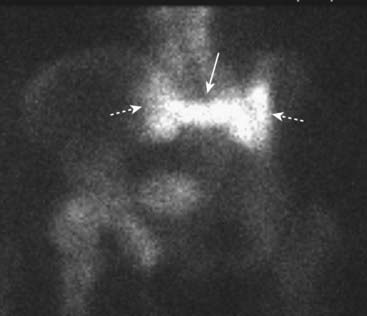

image

Figure 21-26 Sacral insufficiency fractures seen with bone scintigraphy.

There is increased radiotracer uptake in vertical fractures through the sacral ala (dotted white arrows) and a horizontal fracture through the body of the sacrum (solid white arrow). This has been called the Honda sign because it resembles the carmaker’s insignia. Insufficiency fractures occur in abnormal bones that undergo normal stress. The sacrum is a common site for such fractures in osteoporosis.